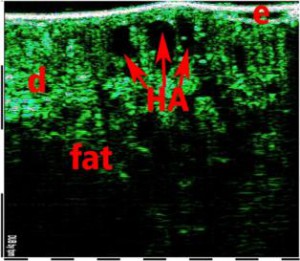

-Έγχυση Πληρωτικών Υλικών (Fillers)